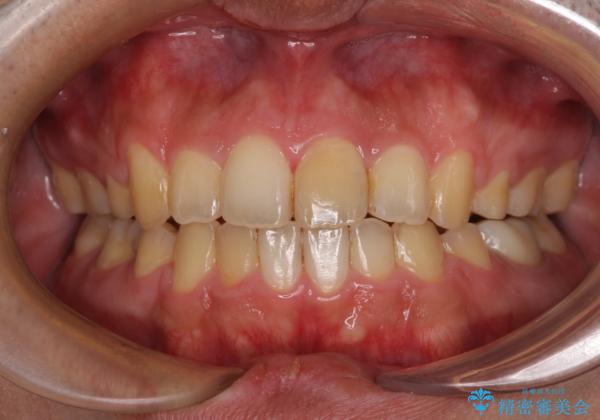

後戻りでデコボコの前歯 インビザライン矯正治療

- 高校時代に行った抜歯矯正が後戻りをしたとのことで来院された患者様です。

再矯正であることから、目立ちにくい装置を希望されたため、インビザラインにて矯正治療を行うこととしました。

下顎骨が左側に変位しているため、正中が合わないことは予想できましたが、歯列が整った後も咬み合わせが安定せず、咬み合わせを落ち着かせるために1年以上の期間を要しました。

噛みにくさの改善に時間がかかってしまうことがインビザラインの欠点の1つといえます。